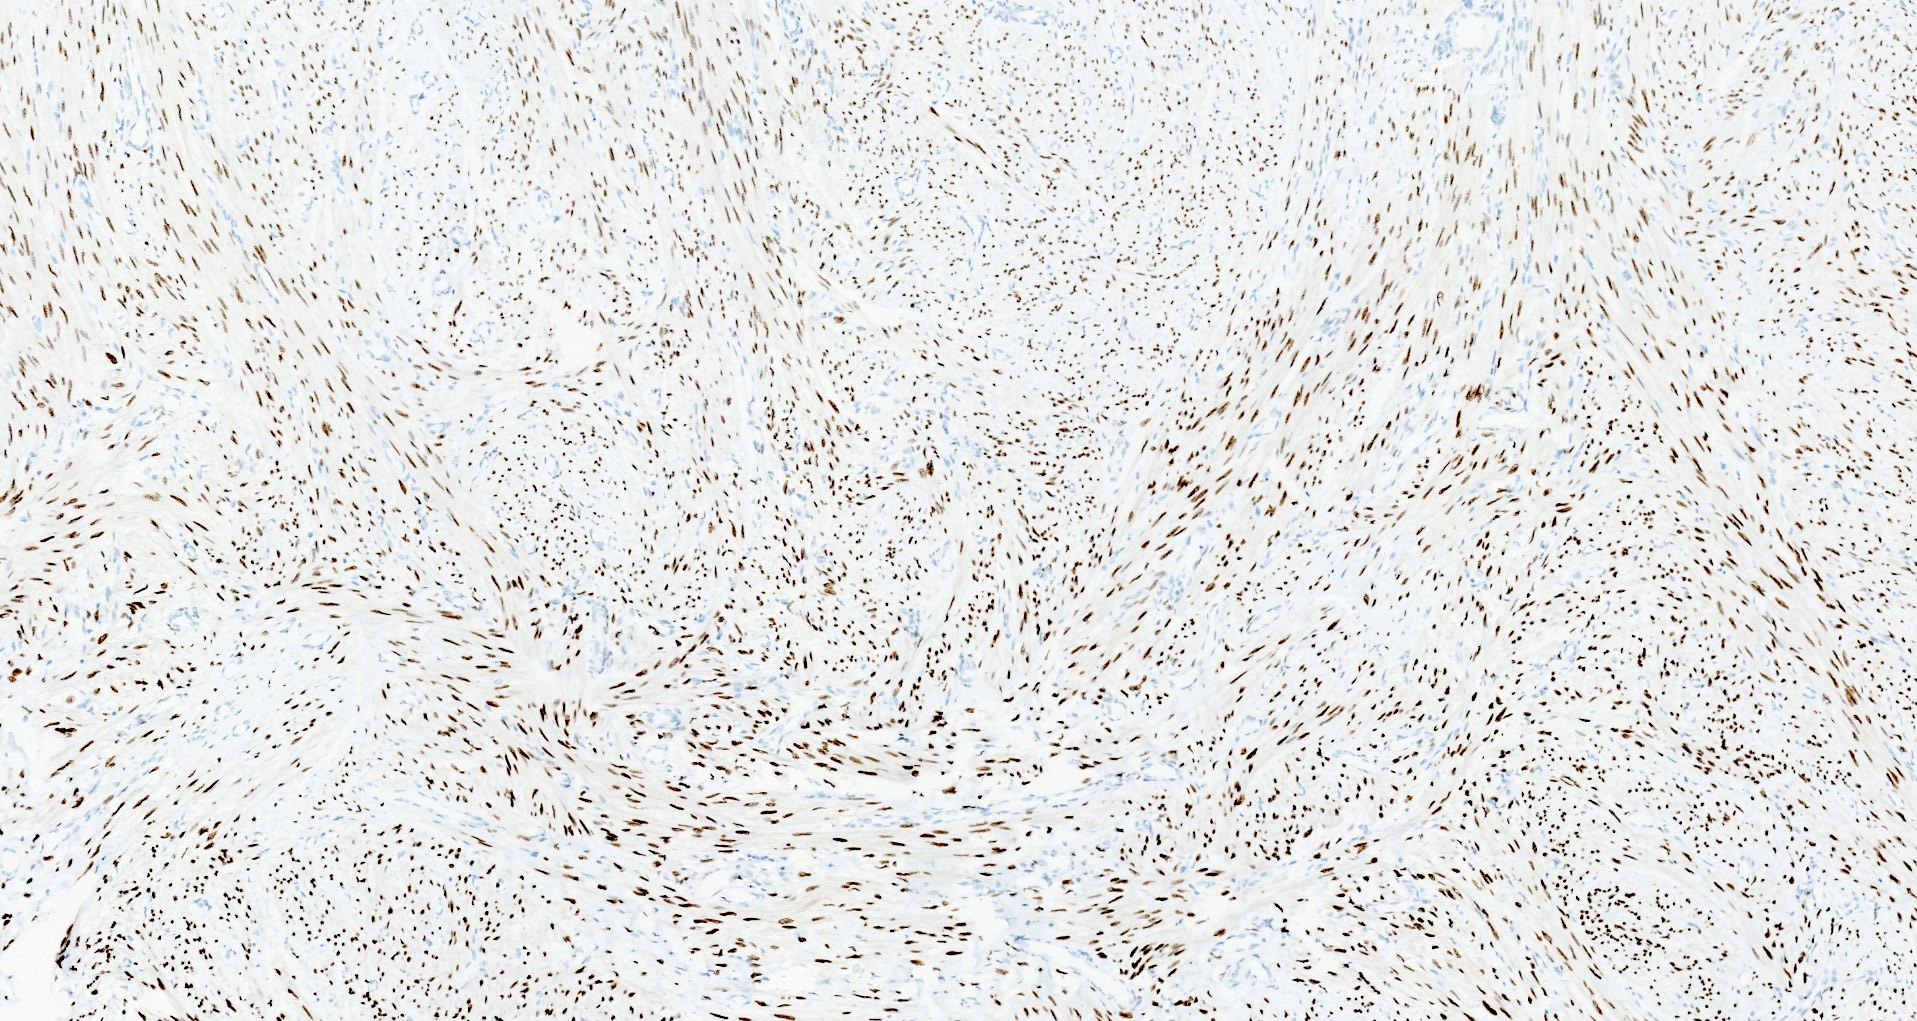

Microscopic (histologic) images

Contributed by Sabrina Croce, M.D., Ph.D., Kristina Doytcheva, M.D., Jennifer A. Bennett, M.D. (Case #508) and @Andrew_Fltv on Twitter

Microscopic (histologic) description

- Conventional / usual leiomyoma (spindle):

- Well defined borders

- Normocellular

- Intersecting fascicles of monotonous spindle cells with indistinct borders, eosinophilic cytoplasm, cigar shaped nuclei (with tapered ends) and small nucleoli

- Atypia: absent or mild

- Mitoses: rare (in general < 5/10 high power fields)

- Blood vessels with thick walls

- With or without infarct type necrosis, hyalinization, calcification, cystic change